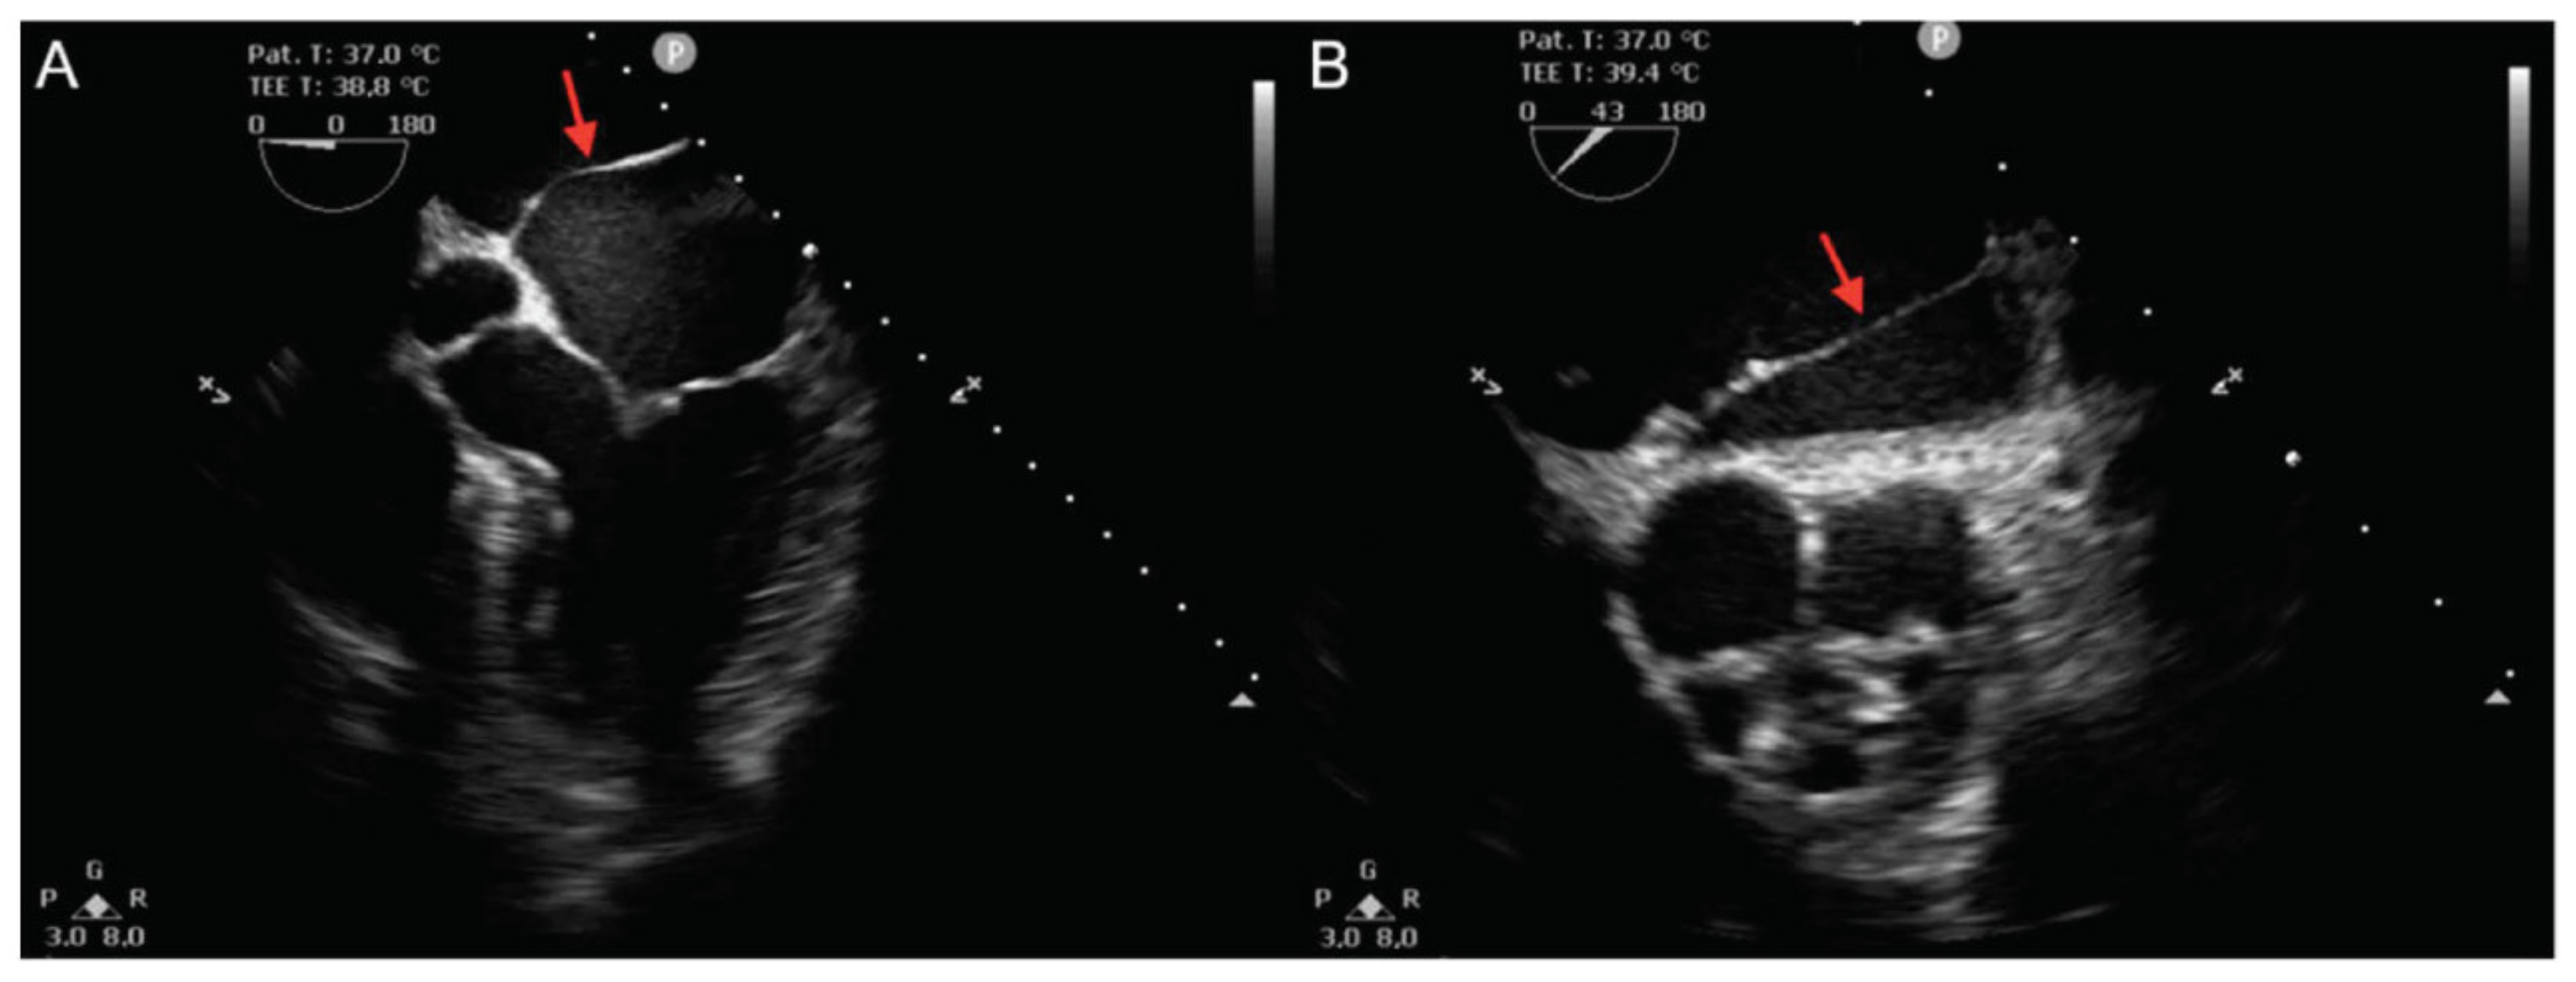

2. Case Presentation